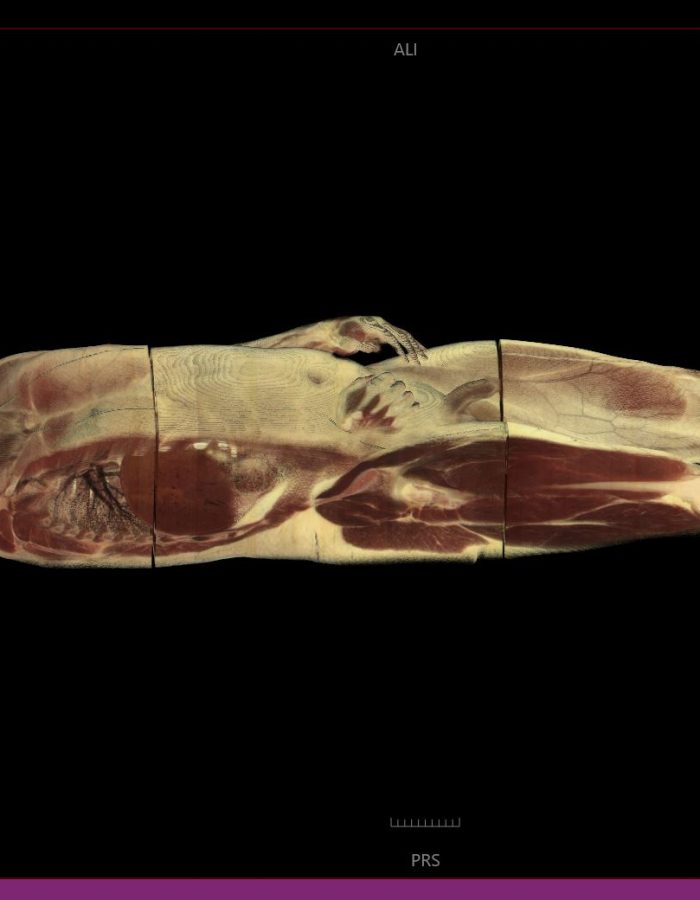

_ Amplia variedad de imágenes con un estilo profesional, tanto para estudios de casos pre operatorios como para estudio profundo de medicina.